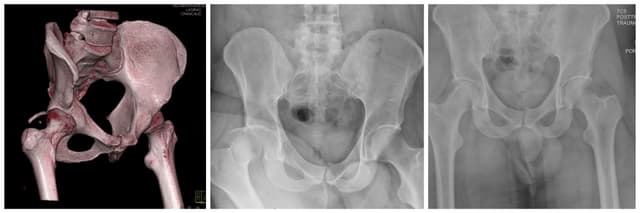

Posterior Wall Acetabulum ORIF

Pre-op

Post-op